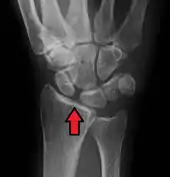

Scapholunate ligament disruption associated with a Colles' fracture

Rupture of the scapholunate ligament causes scapholunate instability, which, if untreated, will eventually cause a predictable pattern of wrist osteoarthritis called scapholunate advanced collapse (SLAC).[2]